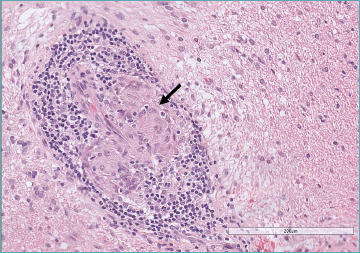

Primary angiitis of the central nervous system (CNS) is an uncommon inflammatory disorder, with highly variable clinical presentation. It needs to be differentiated from several mimickers, such as CNS involvement in systemic vasculitides, connective tissue disorders, infectious disease, and leukodystrophy as well as neoplastic diseases. The diagnosis requires a combination of clinical and laboratory investigations, multimodal imaging, and histopathological examination, which should be available for confirmation. In the present paper, the histopathological features of primary angiitis of the CNS are described and highlighted to help pathologists avoid misdiagnosis of a treatable acquired disease.

Abstract Image